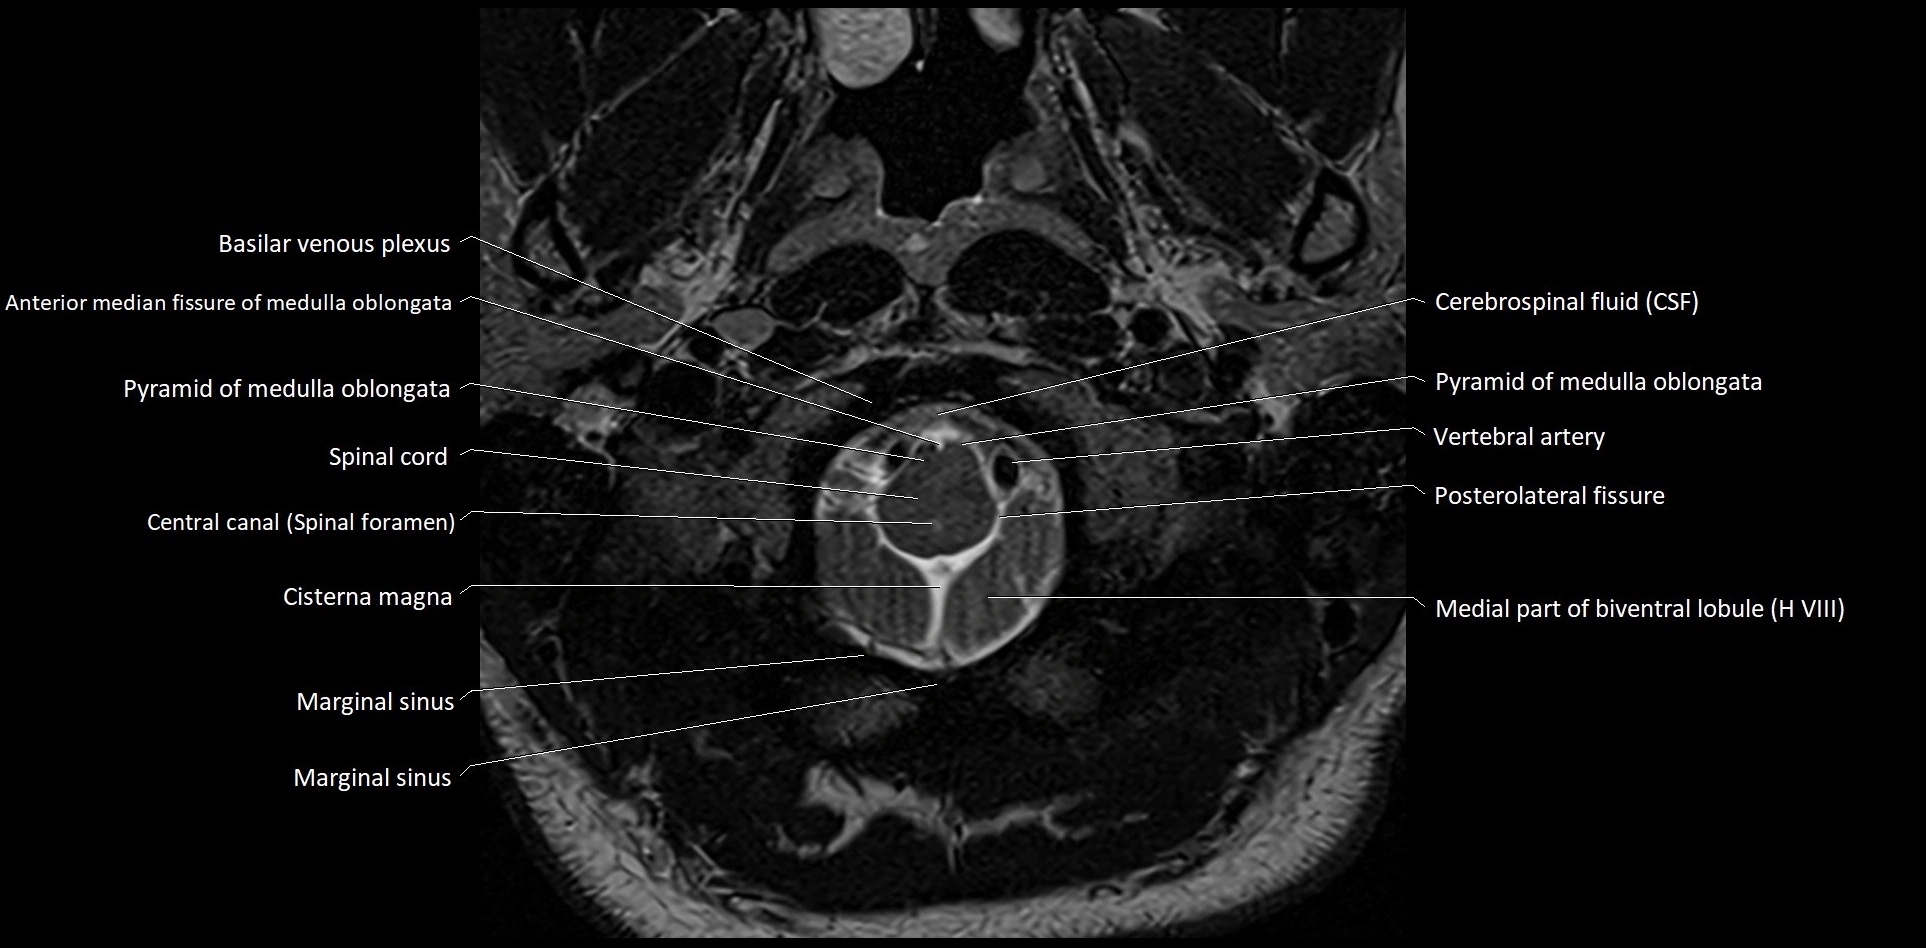

- Marginal sinus

- Medial part of biventeral lobule

- Posterior cerebellomedullary cistern (cisterna magna)

- Posterolateral fissure

- Pyramid of vermis (VIII)